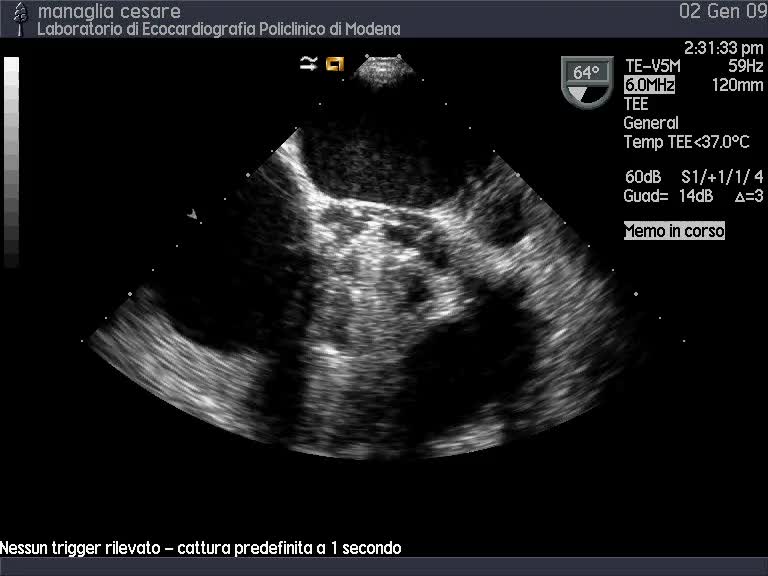

Il trattamento percutaneo delle protesi biologiche degenerate in posizione mitralica

Protesi mitralica meccanica normofunzionanteAutore: Daniela Torta

Categoria: Videoalbum

Parole chiave: diagnosi ecotee meccanica protesi -